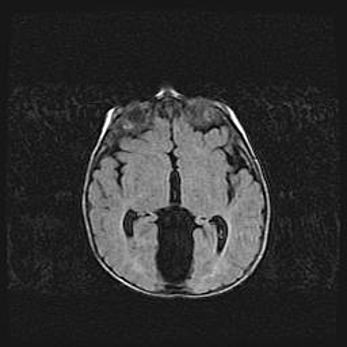

Множественные кисты обоих полушарий головного мозга, наибольшая из них в правой затылочной области. Ассиметричная атрофическая гидроцефалия.

Возраст: 7 месяцев

Вес: 5660 г

Пол: мужской

Окружность головы: 41,5 см

Срок гестации: 28-29 недель

Кисты головного мозга развиваются в результате многоочаговых некрозов вещества мозга и возникают вследствие перенесенной перинатальной инфекции, менингитов, энцефалитов, асфиксии, родовой травмы, расстройств мозгового кровообращения различного генеза. Образованию кист в веществе головного мозга плодов и новорожденных способствуют такие факторы, как высокое содержание в нем воды, недостаточная (или отсутствие) миелинизация и слабая астроглиальная реакция на повреждение.

Кисты могут сочетаться с гидроцефалией и другими поражениями головного мозга.